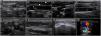

PreprocedureA convex or a phased-array probe is used to assess the view where the effusion accumulation is maximal and closest to the transducer. The thickness of the effusion is measured in diastole in each window, while the distance from the skin to the parietal pericardium and to the myocardium (visceral pericardium) should be obtained to estimate the needle depth of insertion and needle length (Fig. 2A–C). Qualitative assessment should also be performed. While anechoic fluid can be either a transudate or an exudate, the presence of debris or septations points towards the latter. Quantitative and qualitative assessments aid in decision making regarding whether pericardiocentesis, another procedure, or no procedure should be performed. Using a linear probe, the pleura, internal thoracic vessels, and intercostal vessels are delineated to exclude these structures from the needle trajectory (Fig. 2D, E.50

Ultrasound-guided pericardiocentesis. A) Subcostal 4 chamber view. B) Parasternal long-axis view. C) Apical view. As noted, the optimal window to insert the needle is the apical, given the shorter distance to reach the pericardial space (continuous green line) and higher pericardial fluid thickness (continuous yellow line). RA, right atrium; RV, right ventricle; LA, left atrium; LV, left ventricle; RVOT, right ventricular outflow tract. Asterisks indicate pericardial effusion. Adapted from Blanco P, Figueroa L, Menéndez MF, Berrueta B. Pericardiocentesis: ultrasound guidance is essential. Ultrasound J. 2022;14(1):9. https://theultrasoundjournal.springeropen.com/articles/10.1186/s13089-022-00259-5. (CC-BY-4.0). D) Recognition of the left internal thoracic vessels along the left parasternal line (dotted white line) with a linear probe on two-dimensional and color Doppler imaging; s-sct, skin-subcutaneous tissue; m, intercostal muscle; r, rib; arrowhead, pleura; asterisks, internal thoracic vessels. E) Recognition of the intercostal vessels with a linear probe on color Doppler imaging. Real-time in-plane ultrasound-guided pericardiocentesis via intercostal approach (apical view) using a linear probe. The needle (arrows) is entirely observed in the pericardial space (asterisks); LV: left ventricle. G) Hemorrhagic fluid is freely evacuated from the pericardial space after catheter placement.

PreprocedureThe patient should lie supine in a slight semi-recumbent position. With a convex or phased-array probe, it is of paramount relevance to estimate the size of the pleural effusion to define whether thoracentesis is needed or safe, another procedure, or no procedure should be performed. While often eyeballed, a drainable pleural effusion may be defined when the distance between the visceral and parietal pleura is ≥10 mm.55 In addition, the ultrasonographic characteristics of the effusion should also be assessed based on the presence of septations, swirling debris (i.e., plankton sign) or pleural thickening. While anechoic effusions can be either transudative or exudative, those showing one or more of the aforementioned signs are often exudative and should prompt pleural fluid sampling (Fig. 3A and B).53 The distance from the skin to the parietal and visceral pleura should be measured using ultrasound to aid in the selection of an adequate needle length and estimate the depth of insertion (Fig. 3C). The diaphragm must also be delineated. Chest wall vessels should be excluded from the needle trajectory, which is assessed with a linear probe using color Doppler (Fig. 3D).56 Bilateral lung sliding should also be determined prior to the procedure.

Ultrasound-guided thoracentesis. A) A simple pleural effusion (asterisks), diaphragm (d) and lung (L) are delineated using ultrasound. B) A complex pleural effusion (asterisk) is observed; d, diaphragm. C) The best fluid pocket for thoracentesis is selected by measuring the distance from the skin to the pleural effusion (asterisk) and the effusion depth; L, lung; d, diaphragm. D) The intercostal vessels are delineated before cannulation using a linear transducer and color Doppler. E) The insertion site is marked on the skin. F) Dynamic ultrasound guidance for thoracentesis. Arrows, needle shaft; arrowhead, needle tip; asterisk, pleural effusion; L, lung. G) The guidewire (arrows) is observed within the pleural effusion (asterisks); d, diaphram. H). A central catheter (arrows) is observed within the pleural effusion (asterisks); L, lung.

The maximal site of fluid accumulation is often eyeballed by ultrasonography (although the smallest fluid depth can be used to quantify the effusion), and the distance from the skin to the parietal peritoneum and visceral peritoneum is measured to aid in the selection of the needle length and estimate the depth of insertion (Fig. 4A).63

Ultrasound-guided paracentesis. A) Ascites is observed (asterisk), and the distance from the skin to the effusion and to a bowel loop (b) is obtained. B) The inferior epigastric vessels (boxes) are delineated into the abdominis rectus sheath using a linear probe on two-dimensional and color Doppler imaging; s, skin; sct, subcutaneous tissue; m, rectus abdominis muscle; asterisk, ascites. C) The insertion site is marked on the skin, and puncture is performed under static guidance. D) Real-time ultrasound-guided paracentesis; arrows, needle shaft; arrowhead, needle tip; asterisk, ascites. E) A locking pigtail catheter is observed within the ascites (asterisks). The arrow indicates the body, whereas the arrowhead indicates the tip of the pigtail.

Using a linear probe, the abdominal wall vessels should also be identified and excluded from the needle trajectory (Fig. 4B).

In transverse and longitudinal views, soft-tissue fluid collections are measured, as well as the distance to the skin, to estimate the needle depth of insertion and to choose an adequate needle length (Fig. 5A,B). Color Doppler aids in defining the presence of vascular structures near the lesion, to avoid puncturing when inserting the needle.

Ultrasound-guided aspiration of soft tissue collections and arthrocentesis. A) Soft tissue fluid collection is identified and measured. B) Distances are measured to estimate the needle depth of insertion and length to be used. C) Technique for finding the suprapatellar articular recess of the knee and its corresponding ultrasound images; p, patella; t, cuadriceps tendon; f, femur; asterisk, fat pad (articular recess). D) Knee effusion is indicated by the symbol #. E) Real-time ultrasound-guided arthrocentesis of the knee, obtaining a purulent fluid. The arrowhead indicates the bevel of the needle that reached the articular effusion. F) Real-time ultrasound-guided aspiration of soft tissue collection. The needle is indicated by arrows.

Ultrasound anatomy of each joint should be well known for assessing effusion. Given its frequency and ease of access, knee ultrasound is reviewed herein. With the linear probe placed longitudinally above the patella and the probe marker pointing cephalad, the superior portion of the patella, quadriceps femoris tendon (long axis), fat pad, and femur should be observed (Fig. 5C). The effusion will be located below the quadriceps tendon and above the femur (Fig. 5D). Once fluid effusion is recognized, the probe is rotated 90 degrees into a transverse view so that the probe marker faces to the patient's right side. The distance from the skin to the effusion is then measured to estimate the needle depth of insertion and length to be used.

PreprocedureWith the sitting patient or in a lateral decubitus (the latter often in critical care patients), a convex probe is placed in the transverse plane (perpendicular to the long axis of the spine) in the midline of the lower back. Here, the spinal processes (SPs) are recognized as superficial hyperechoic peaked structures with posterior acoustic shadowing (Fig. 6A), while the laminae or articular processes (“bat sign”) are seen as hyperechoic structures deep and lateral to the SPs. The hypoechoic interspinal spaces can be delineated by moving the transducer cephalad or caudally to the SPs. With the SPs centered on the ultrasound screen, the skin is marked with a pen at the transducer midpoint over several vertebrae (Fig. 6A).

Ultrasound-guided lumbar puncture. A) With the linear transducer placed transversally over the midline of the lower back, the spinal processes (sp) are recognized and the skin marked with a pen. B) After rotating the transducer 90 degrees clockwise and placing it longitudinally over the midline of the lower back, the spinal processes (sp) are seen, and the interspinal space (arrow) is delineated, and the skin is marked with a pen. C) Intersecting the skin markings obtained in A) and B), the needle insertion site is marked with a pen. D) Parasagittal approach and the corresponding ultrasound image. To obtain this view, the transducer is slightly basculated to one side from the longitudinal midline view. In the ultrasound image, the spinal muscles (spm), laminae (L), posterior complex (white arrows), and posterior longitudinal ligament (black arrows) are well recognized. The distance to the posterior complex is measured (dotted green line), to approximate the needle depth of insertion during the lumbar puncture.

The transducer is then placed longitudinally (parallel to the long axis of the spine). Again, the SPs are observed as bright peaked structures with posterior acoustic shadowing; between them, there are the hypoechoic interspinal spaces (Fig. 6B). To recognize the sacrum, the transducer is moved caudally until a roughly hyperechoic line is observed. With the interspinal space centered on the ultrasound screen, the skin is marked with a pen at the transducer midpoint over several vertebrae.

After marking the skin in the transverse and longitudinal planes, both lines are continued until they intersect the midline, where the puncture will be performed over the broad spinal space (Fig. 6C).

Slightly angling the transducer to the midline, the paramedian longitudinal approach is obtained (Fig. 6D). Here, the pedicles and posterior complex (including the ligamentum flavum, epidural space, and posterior dura) are easily recognized (Fig. 6D) Measuring the distance from the skin to the posterior complex aids in estimating the needle depth of insertion and length to be used.(Fig. 6D)